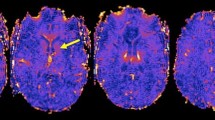

Of all 193 lesions, 11.4% were classified “iron dot” lesions (see Table 3). The “iron dot” sign was present in 71.4% (5/7) of the SuS patients, compared to 0% in our control cohort. Thus, sensitivity was 71.4% and specificity 100%. A median number of 2 (range: 0–9) iron dot lesions per patient was found in our cohort. This lesion type accounted for a median of 5.41% (range: 0-56.3%) of all cerebral lesions in an individual patient. While mean volume suggests a difference in lesion size in favor of non-iron lesions, the median volumes of iron versus non-iron lesions were comparable. Iron dot lesions were predominantly visualized in callosal and ‘other white matter lesions’ (see Table 3, Figs. 1 and 2, and Supplemental Fig. 1).

“Iron dot” lesion in the left frontal lobe on 3D T2* weighted coronal (top left), sagittal (lower left), and axial (right) 7 Tesla magnetic resonance imaging sequences. Please note the strong but punctate and sharply delineated intra-lesional signal loss on T2*w. This type of intra-lesional T2*w signal loss differs from that of more recent multiple sclerosis (MS) lesions where central T2*w hypointensities appear larger and more diffuse. They are also distinct from (enlarged) venules present in MS lesions as “iron dot” lesions do not show a tubular appearance following the course of a vessel